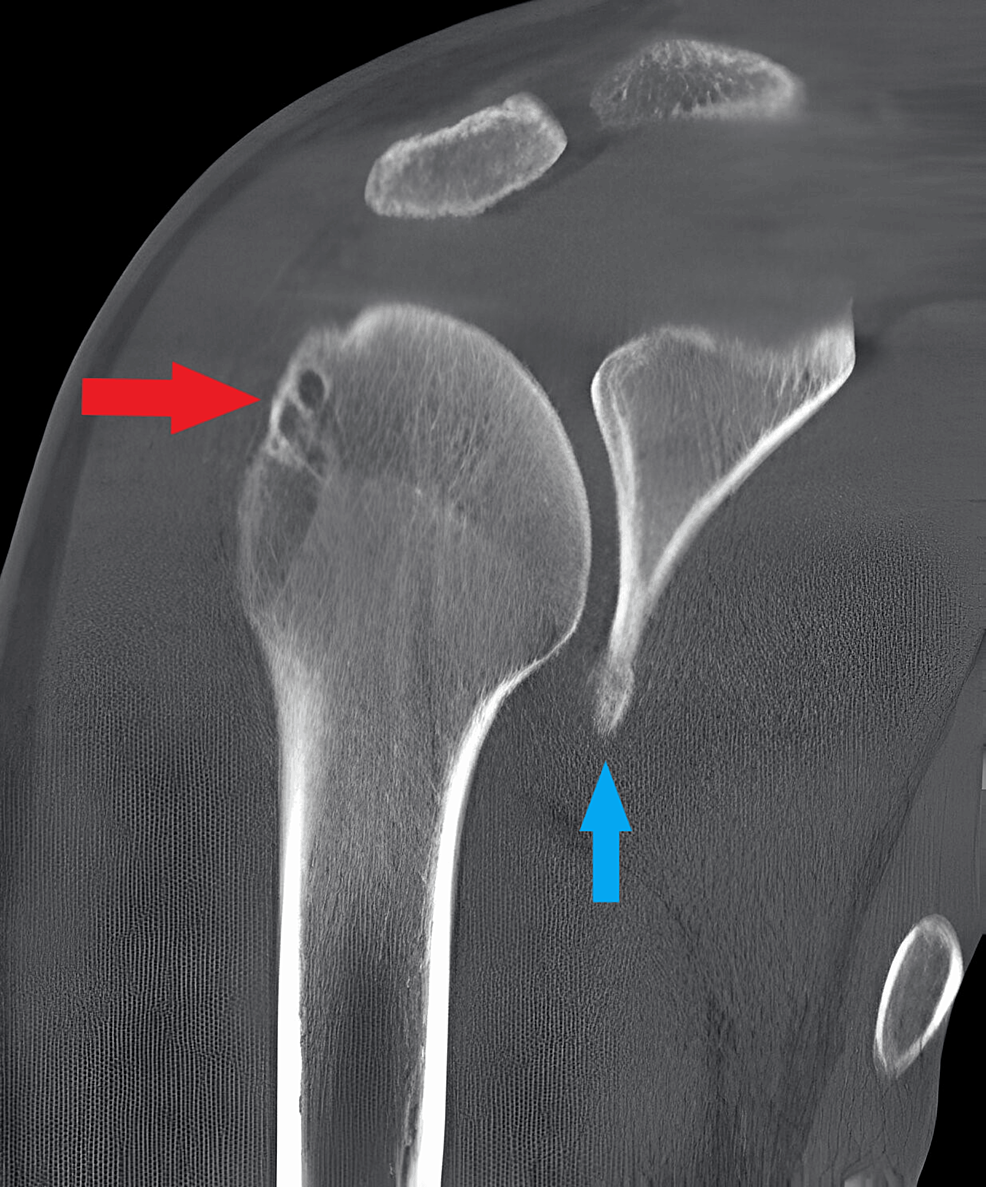

Postoperative images of patient 3 at 35 days following open Latarjet Open Latarjet Procedure Cpt take the cephalic vein laterally and ligate the large medial branch. (2) osteotomy and subsequent release; (1) coracoid exposure and initial release; Dissect the interval between the deltoid and the. ohio state’s latarjet anterior shoulder stabilization rehabilitation guideline is to be utilized following open anterior shoulder. i need to make sure i am billing the right cpt. Open Latarjet Procedure Cpt.